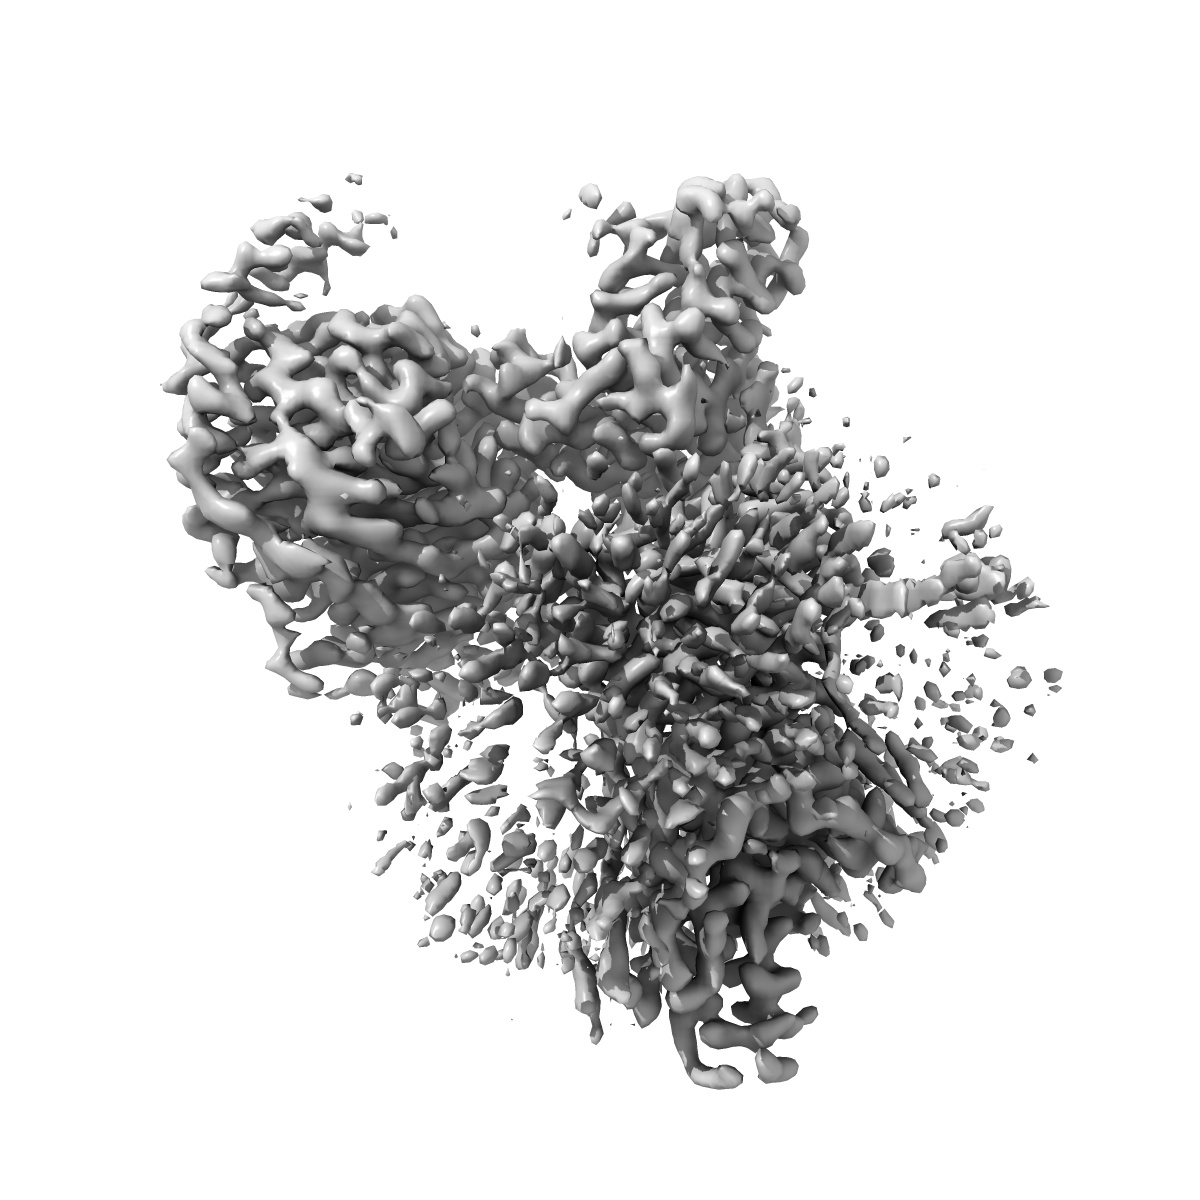

Cryo-EM structure of the human adenosine A1 receptor-Gi2-protein complex bound to its endogenous agonist and an allosteric ligand

Single-particle3.2 Å

Sample: Human adenosine A1 receptor-Gi2-protein complex bound to its endogenous agonist adenosine